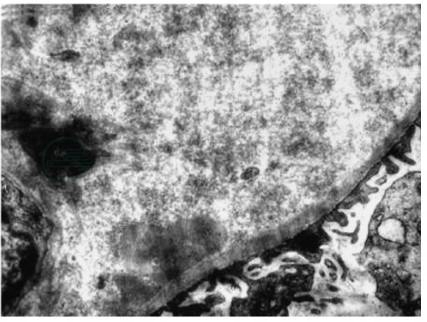

肾活检病理检查:免疫荧光:IgG(+),IgA(-),IgM(-),C3(++),C1q(-),Fibrin(-),轻链蛋白κ(-),λ(-)。光镜:15个肾小球,肾小球系膜细胞增生,系膜基质增多尤为明显,呈结节状硬化,部分节段性插入,基底膜节段性增厚,双轨征形成。结节硬化的系膜区PAS和Masson染色呈红色。肾小管上皮细胞空泡和颗粒状变性,多灶状和大片状萎缩,可见多数蛋白管型。肾间质多灶状淋巴和单核细胞浸润伴纤维化。小动脉管壁增厚,节段性玻璃样变性(图1)。

图1 纤连蛋白肾小球病:肾小球系膜结节样硬化(PASM×400)

刚果红染色阴性。电镜:病变的肾小球内未见电子致密物,系膜区和基底膜内可见大量杂乱排列的短纤维样物质,纤维直径5~8nm,上皮细胞足突弥漫性融合(图3)。病理诊断:纤连蛋白肾小球病。

图3 纤连蛋白肾小球病:肾小球系膜区短纤维样物质沉积(电镜×10 000)